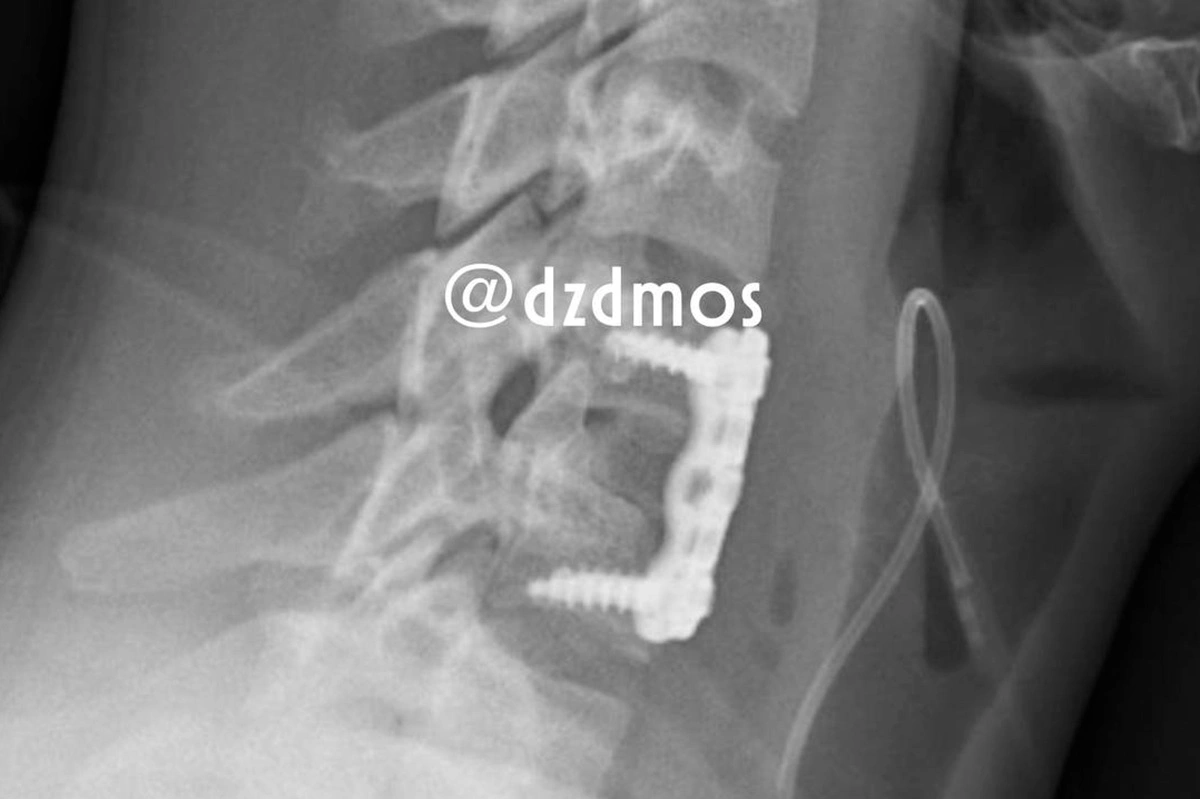

Рентгенограмма после установки аутотрансплантата

Контрольная рентгенограмма показала, что установка аутотрансплантата оказалась успешной и позвонки закреплены посредством накостной пластины. Мальчика выписали, когда стало понятно, что у него больше нет боли в шее и травме не представляет собой угрозы качеству его жизни.